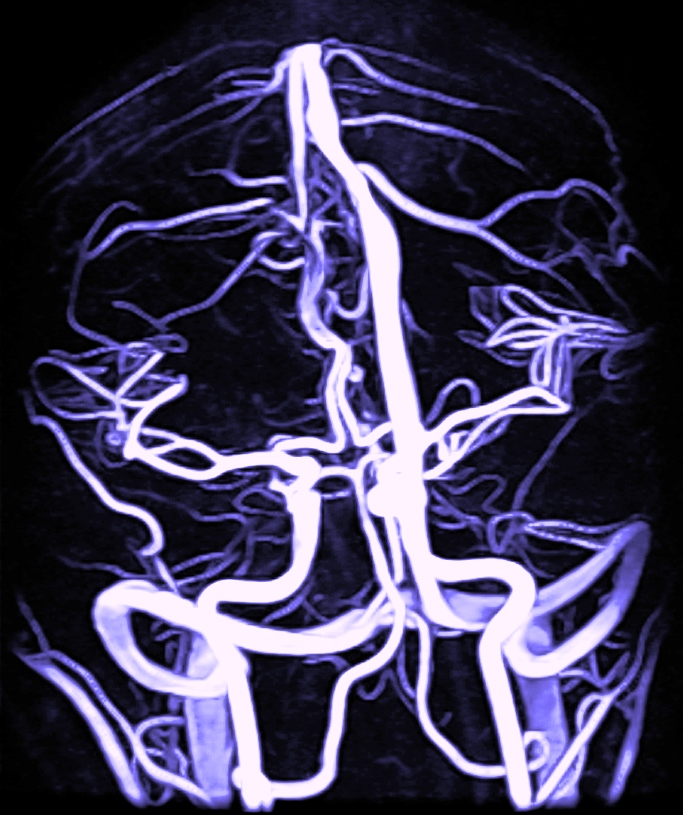

¢‘est environ maintenant, un peu avant ou bien dans pas longtemps que la bascule s’opère. Sharon aime bricoler, et la voilà œuvrant à je ne sais quelle réparation quand une mine, un minuscule amas de fibrine rompt ses amarres. Subrepticement le voilà qui fait chemin en direction du cervelet. Ce thrombus millimétrique maudit va profiter d’une position improbable de la bricoleuse pour traverser le cœur sans quasiment faire de dégât. Shaun (sa mère irlandaise l’appelle parfois aussi Yoanne) ressent juste une légère crampe au thorax, une crispation de la hanche et quelques nauséeux relents, mais les douleurs n’ont aucune prise sur elle lorsqu’elle travaille…; le flotteur de continuer son voyage fantastique vers de plus fins vaisseaux, jusqu’à ce coin de bourrichon tout près du reptilien de tous les héritages, puis se poser et jouer les castors à barrage, tel une vermine de demi-rat femmenivore.